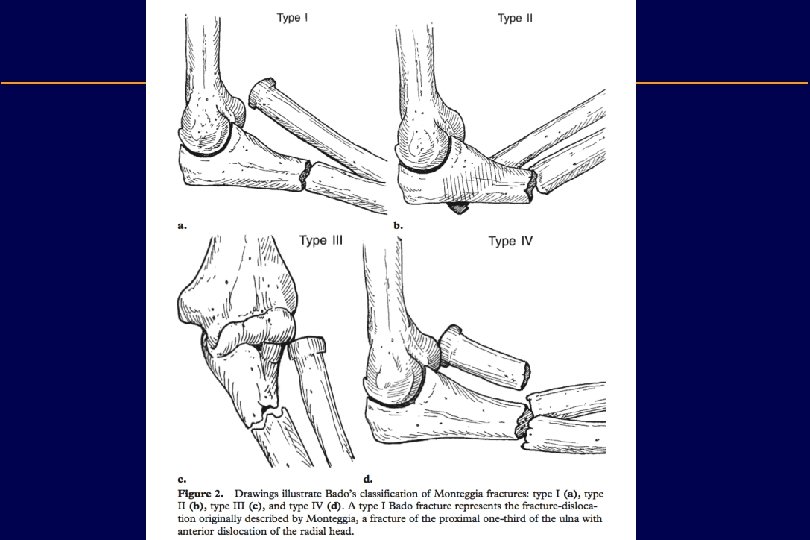

Radius and ulnar shaft fracture Diagnosis • It is important always to X-ray the whole shaft of both radius and ulna and to include both the wrist and the elbow. • Avoid missing: n Monteggia fracture: A dislocated head of radius with an isolated fracture of the ulna n Galeazzi fracture: A dislocated distal radio-ulnar joint with an isolated fracture of the radius